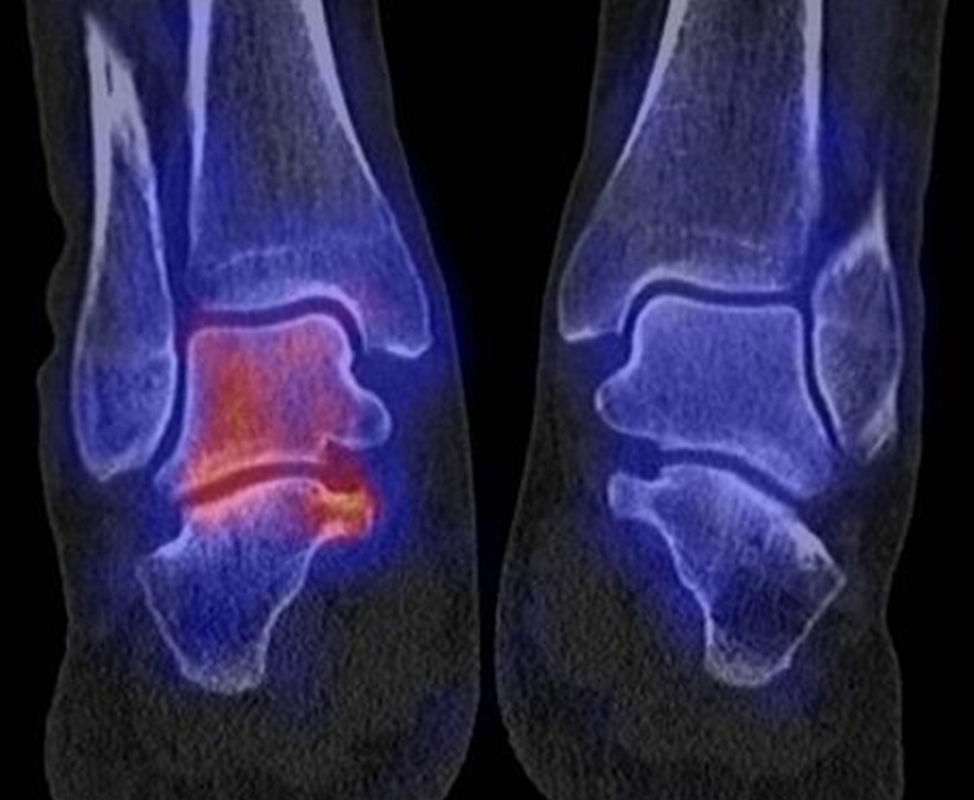

Die Abbildungen 4.2.a bis d zeigen den typischen Aspekt einer talacalcanearen Coalitio. Es besteht nur eine linksseitige, symptomatische Coalitio talocalcaneare (4.2.a und c); das 35 Tage zuvor angefertigte MRT zeigt keine auffälligen Signalveränderungen (4.2.b und d).